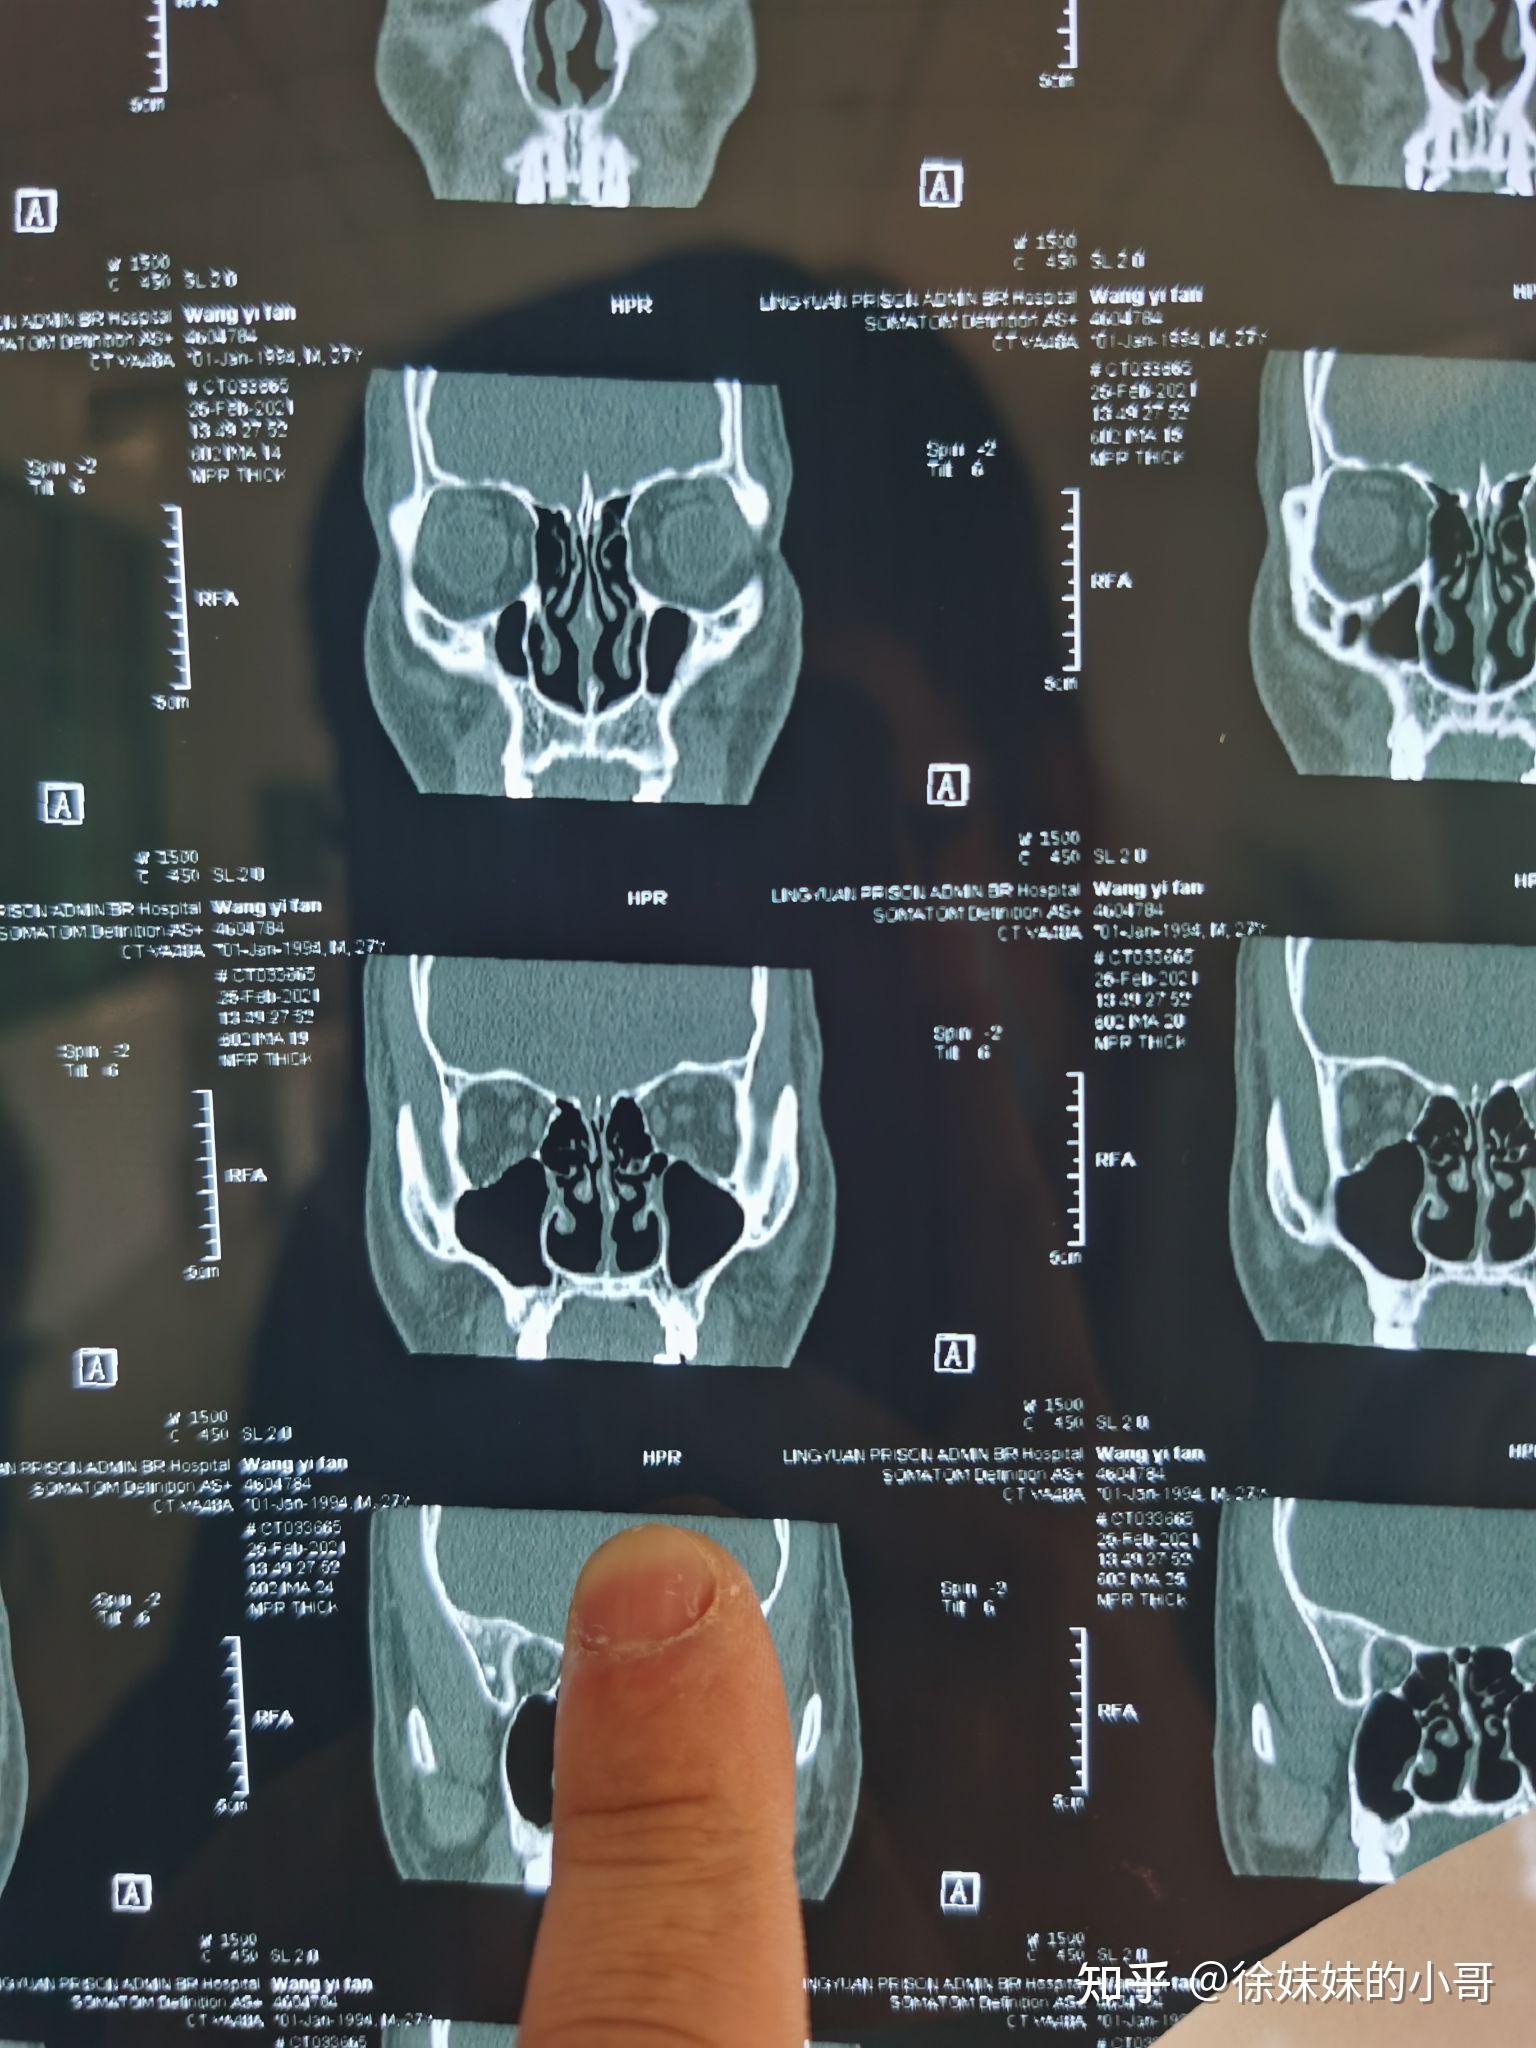

王医生你好就是医院开给我的这个ct算是鼻窦冠状位ct么如